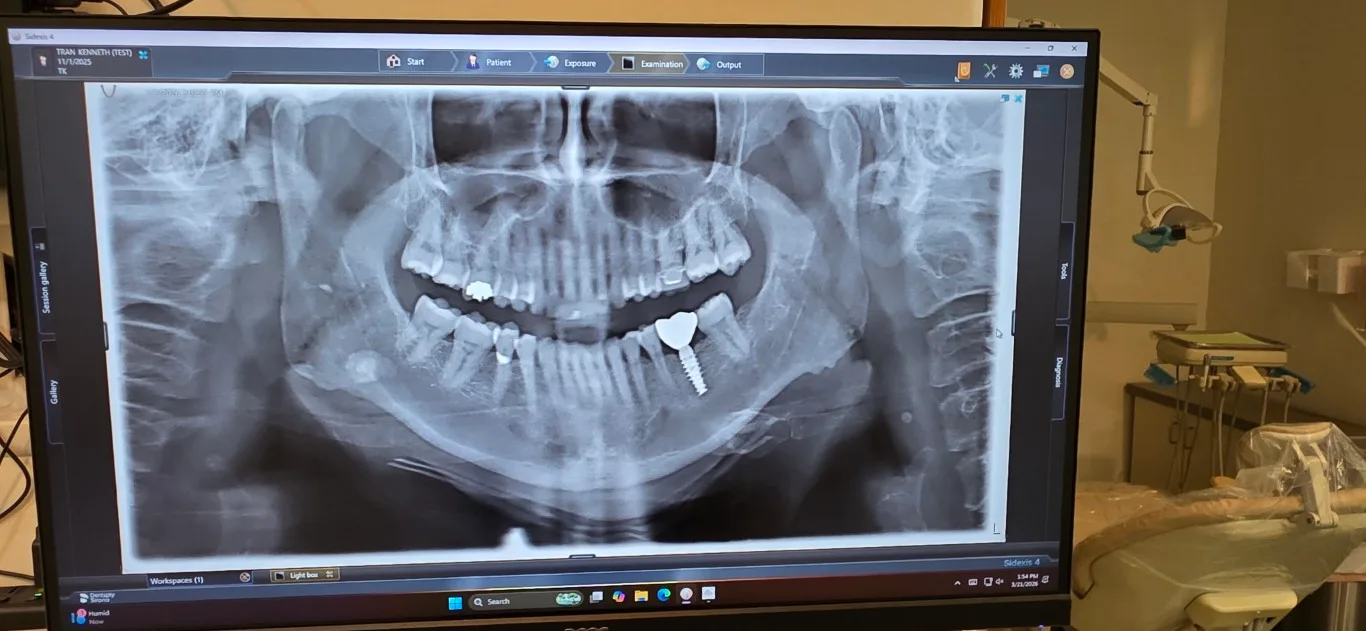

Digital X-ray showing dental implant placement at Peninsula Dentistry

Dental implants are titanium posts surgically placed into the jawbone to permanently replace missing teeth. Each implant supports a custom zirconia crown that looks, feels, and functions like a natural tooth. At Peninsula Dentistry in Huntington Beach, Dr. Tran has placed thousands of implants over his 20-year career using 3D imaging and digital planning for precise, long-lasting results.

Whether it's a single tooth or a full-arch restoration, we plan everything with 3D imaging and digital scans before we place anything. No guesswork. The titanium post fuses with your jawbone over a few months, and then we top it with a custom zirconia crown that matches your other teeth perfectly.